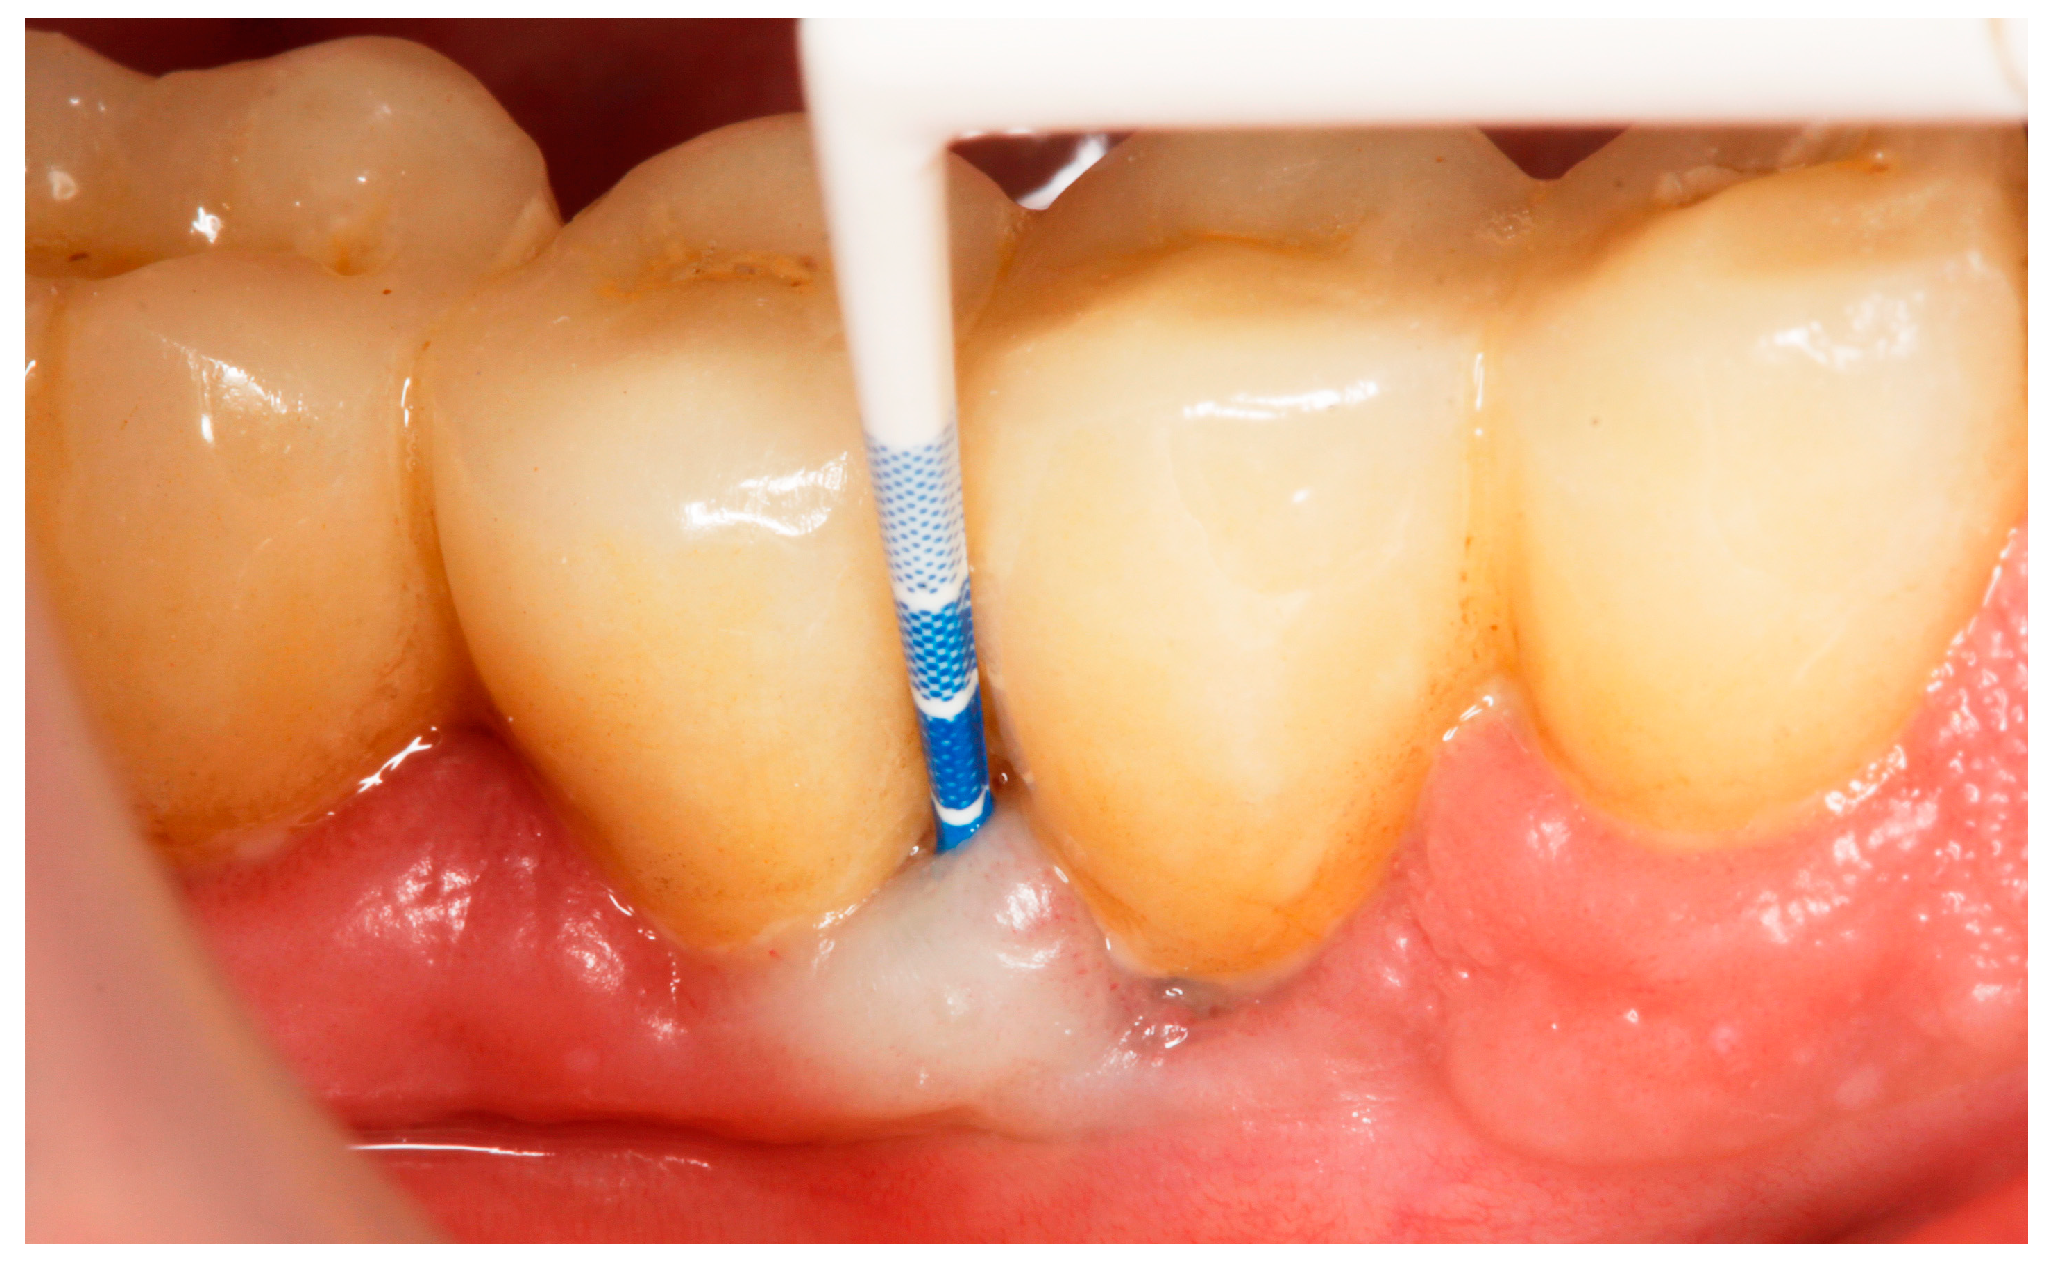

2.8. Treatment Procedures

- PMPR, individualized OH recommendations, for entire dentition/implants;